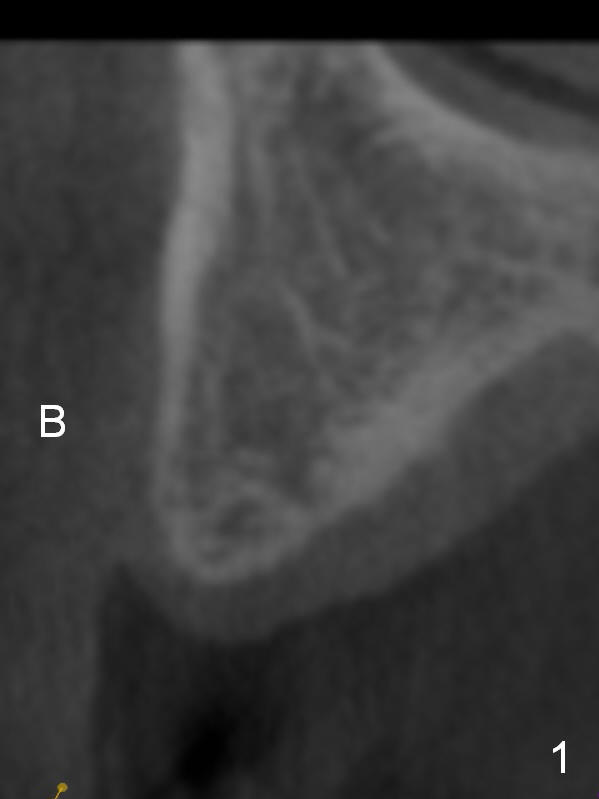

The fearful patient is satisfied with implant placement at #29 and will return to have #5 implant placed. Fig.1 is coronal section of the site of #5 (B: buccal). It shows the narrow crest and low bone density (40-200 Hounsfield unit). Start bone expansion with #15 blade slightly palatal (Fig.2 green line), followed by bone scalpels and bone blades. The latter leads to differential expansion of the buccal and palatal plates (Fig.3 arrows). Once the crestal bone is expanded, use drills or osteotomes (RTs) for deeper portion of osteotomy (Fig.4 red arrow). Finally an appropriately-sized implant is placed (Fig.5). Also prepare bone expanders. Upper Arch Reconstruction, Upper Premolar Immediate Implant Xin Wei, DDS, PhD, MS 1st edition 04/08/2016, last revision 06/12/2019